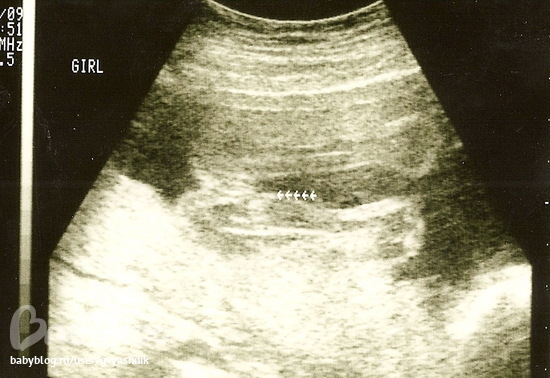

Для сравнения Маша 20 недель

девочка)